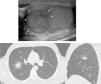

We report the case of a 29-year-old man presenting with palpation of an indurated mass in the right testicle. An ultrasonography was performed, revealing a pseudonodular change in testicular echostructure, compatible with testicular tumor disease (arrows, Fig. 1A). The examination was completed with a chest and abdomen computed tomography (CT) scan, showing a single pulmonary nodule in the right upper lobe, with a peripheral ground-glass halo compatible with hemorrhagic metastasis (Fig. 1B and C). The patient underwent orchiectomy and the histological examination showed anaplastic seminoma with a choriocarcinoma component.

The halo sign on the CT is an unspecific sign associated with disease entities such as aspergillosis, candidiasis, tuberculoma with symptoms of hemoptysis, lymphoma or bronchoalveolar carcinoma.1 This is evidenced on CT by a dense nodule with a peripheral ground-glass halo.2 Angiosarcomas and choriocarcinomas, as in the case described here, are the tumors that most frequently produce this sign.